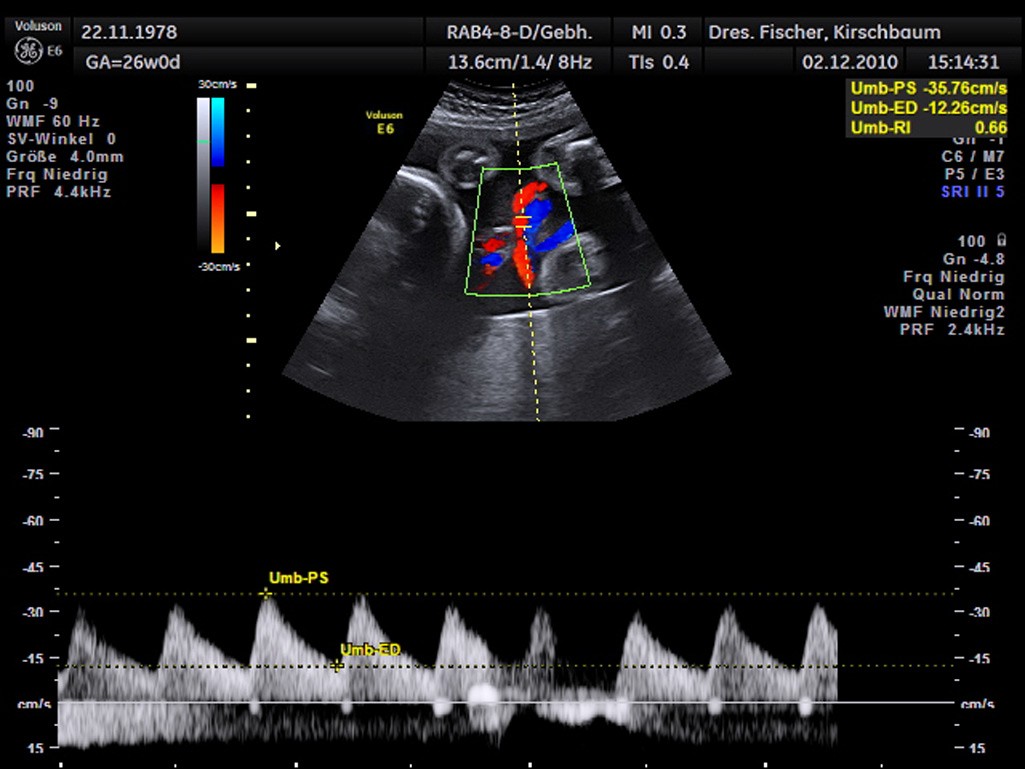

Die Dopplersonographie ist eine besondere Form des Ultraschalls, bei der vor allem die Blutflussgeschwindigkeit der Nabelschnur gemessen wird.

Die Untersuchung wird im Allgemeinen ab der 20. SSW eingesetzt. Man kann mit der Untersuchung z.B. eine Unterversorgung des ungeborenen Kindes ausschließen.